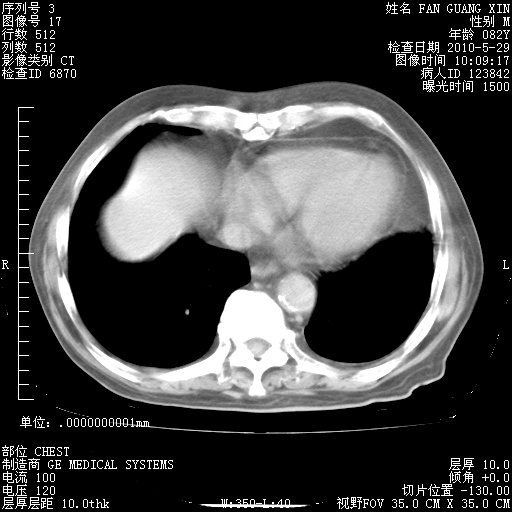

还需要哪些辅助检查?我们医院排除真菌感染没有任何检验方法,胸片好像能够排除肺部真菌感染。